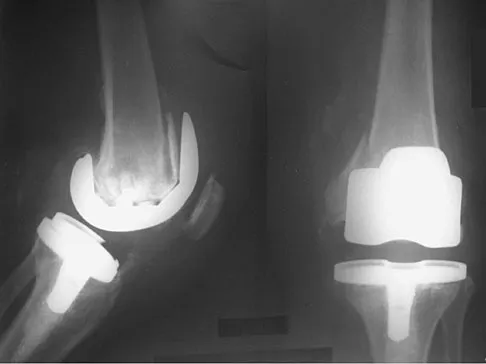

Question 59 High Yield

Figures 5a and 5b show the radiographs of an active 52-year-old man who has increasing knee pain and progressive varus deformity after undergoing total knee arthroplasty 7 years ago. Examination reveals a small effusion, but he has good motion and stability. What is the most likely diagnosis?

Detailed Explanation

The radiographs show narrowing of the medial joint space, which indicates polyethylene wear and progressive varus alignment. Wear particles incite osteolytic lesions like the one seen on the lateral radiograph. O'Rourke MR, Callaghan JJ, Goetz DG, et al: Osteolysis associated with a cemented modular posterior-cruciate-substituting total knee design. J Bone Joint Surg Am 2002;84:1362-1371.